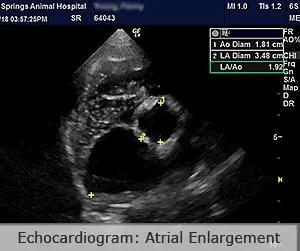

Cardiac Radiology (Xrays)Radiographs provide information on heart size, shape, and position. Abnormalities indicate specific changes within the heart due to heart disease. Radiographs also allow visualization of the lungs and indicate whether fluid is backing up from the heart into the lungs due to heart failure. The high def images captured with our equipment allow visualization of more subtle or early changes than low def images captured on standard radiology equipment. Echocardiography (Ultrasound of the heart)Echocardiography is a non-invasive specialized ultrasound imaging technique which allows visualization of the heart including the walls, chambers, and valves.

The following echocardiogram performed by Dr Stuart Ryder shows an abnormally thickened mitral valve. Color flow doppler demonstrates abnormal blood flow through the valve from the left ventricle backward into the left atrium. This dog’s abnormal measurements on radiographs (VHS) and echocardiogram (LA/AO ratio, LVIDDN) indicated it was a good candidate to start pre-symptomatic treatment with pimobendin. |